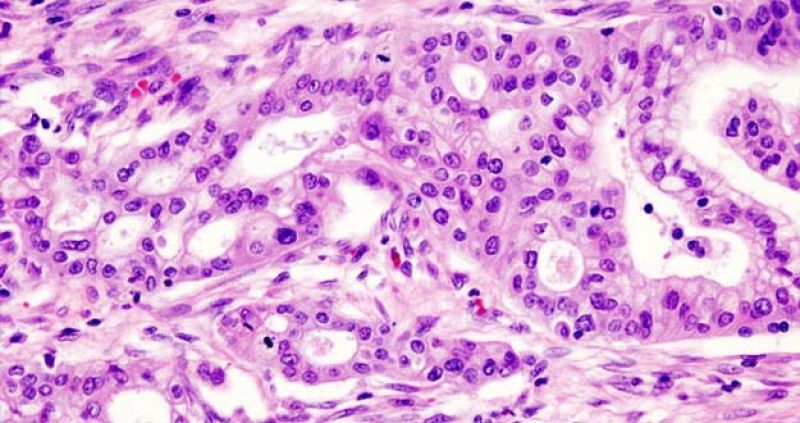

Imagen de un adenocarcinoma de páncreas.

Imagen de un adenocarcinoma de páncreas. Wikimedia Commons